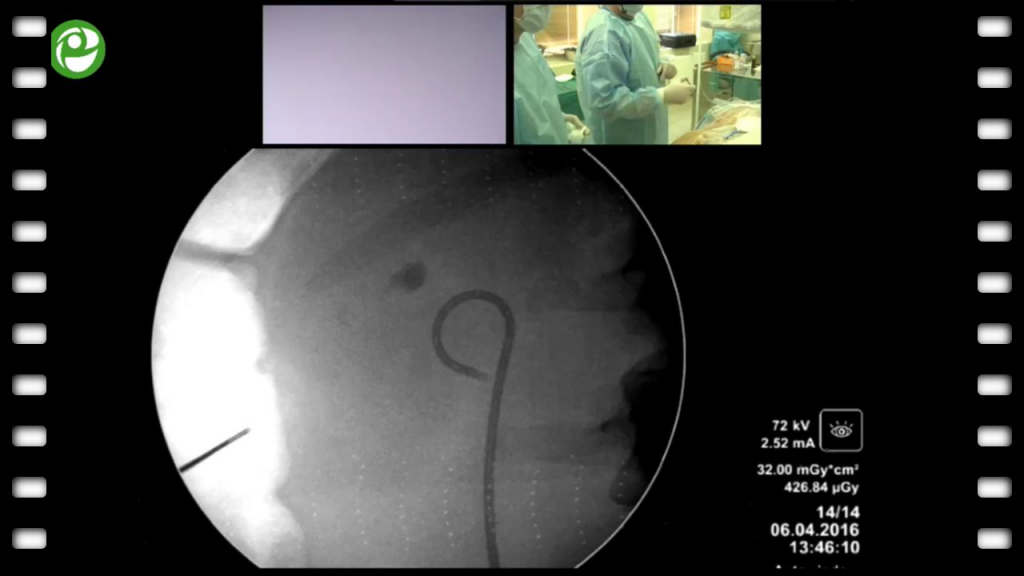

Перкутанная ультрамининефролитотрипсия слева

04 мая 2016